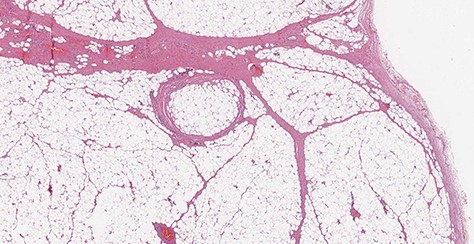

A 77-year-old man was referred for a long history of heartburn and more recent onset of progressive regurgitation, dysphagia and weight loss. Empirical therapy with proton-pump inhibitors was ineffective. The gastroesophageal reflux disease health-related quality of life (GERD-HRQL) score was 22. The functional outcome swallowing scale (FOSS) score for dysphagia was 2. Physical examination was unremarkable. Upper gastrointestinal endoscopy showed a soft submucosal bulging in the posterior wall of the distal esophagus located between 29 and 39 cm from the incisors, and 3 cm proximal to the esophago-gastric junction (Fig. 1). Computed tomography of chest and abdomen showed a fat-density submucosal mass with luminal narrowing (Fig. 2). High resolution manometry (HRM) showed pan-esophageal pressurization in 100% of the swallows and a resting lower esophageal sphincter (LES) pressure of 11.2 mmHg (Fig. 3). Through a laparoscopic transhiatal approach, esophageal myotomy, mass enucleation, suture approximation of the muscle layer, posterior cruroplasty, and 270° Toupet fundoplication was performed (Fig. 4). The procedure took 55 min. Postoperative course was uneventful. A gastrographin swallow study on Day 1 showed a normal esophagogastric transit and the absence of leaks. The patient was discharged home on postoperative Day 2. Pathology confirmed the clinical suspicion of esophageal lipoma (Fig. 5). High-resolution manometry was repeated at the 6 month follow-up and showed an ineffective esophageal motility, with 50% of non-conducted swallows. The resting LES pressure increased (17.4 mmHg), and the swallow-induced LES relaxation was normal. The GERD-HRQL score was 3 and the FOSS score was 0.

Microscopic transverse section revealing a benign tumor composed of a large amount of mature adipocytes with a flat peripheral nucleus without atypia, surrounded by fibrous tissue and containing rare blood vessels (H&E stain, ×10).